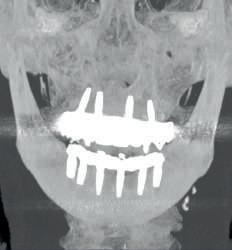

According to the prosthetic planning in the co diagnostix software, it is decided to extract the remaining upper teeth, leaving two teeth temporarily for stabilisation of the surgical guide and as a reference for the immediate scanning after the placement of 4 single-stage implants (Fixo. Oxy. Italy).

In the lower part the extraction of the remaining teeth is planned and the immediate placement of 6 implants (dynamic hex. Cortex . Israel) and and the immediate placement of Multi Units Abutments (MUA. DAS. Dynamic Abutment Solutions. Spain). However, when planning for the lower implants at the same level, there is a collision of the sleeves with the bone that prevents the placement of the implants at the same level (fig. 6), so the offset of the anterior implants is modified to ensure the correct position in the guide, avoiding interference with the bone and placing the implants at the same level (fig. 7).

In the maxillary case, the implants with integrated MUA Abutment (monoimplantes fixo . oxy italia) are placed and scanning is performed before extractions of the remaining teeth that will serve as a reference for the scan and the position reference in the design software.

Once the surgical guide is stabilised, the osteotomies and placement of the lower posterior implants are performed, while the length of the anterior implants is changed in the drilling sequence according to the modified offset, which corresponds to the mounter, colour-coded according to the length of the offset.

Immediately after implant placement, the MUA Abutments are placed (Dynamic Abutment Solutions)

The immediate prostheses are milled in PMMA and fitted on their corresponding bases, adjusted and radiographically checked for proper seating.